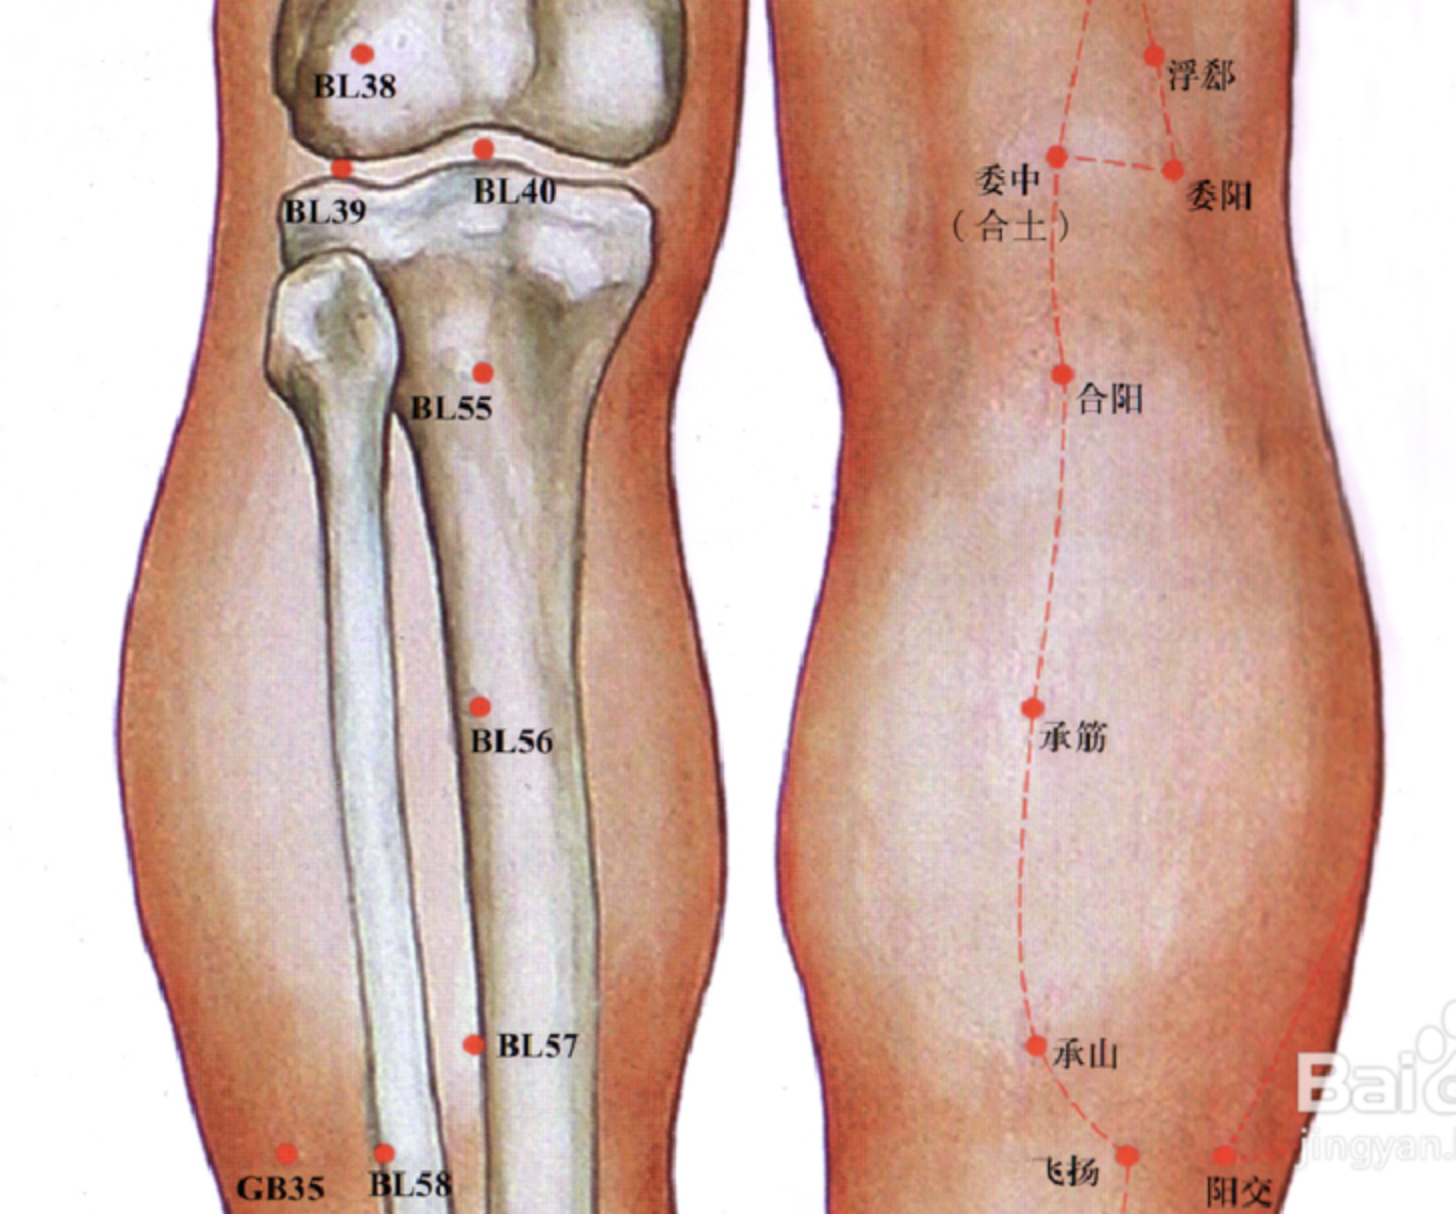

【(七)足太阳膀胱经(图 10-25-1)】

委中

承山

昆仑

至阴